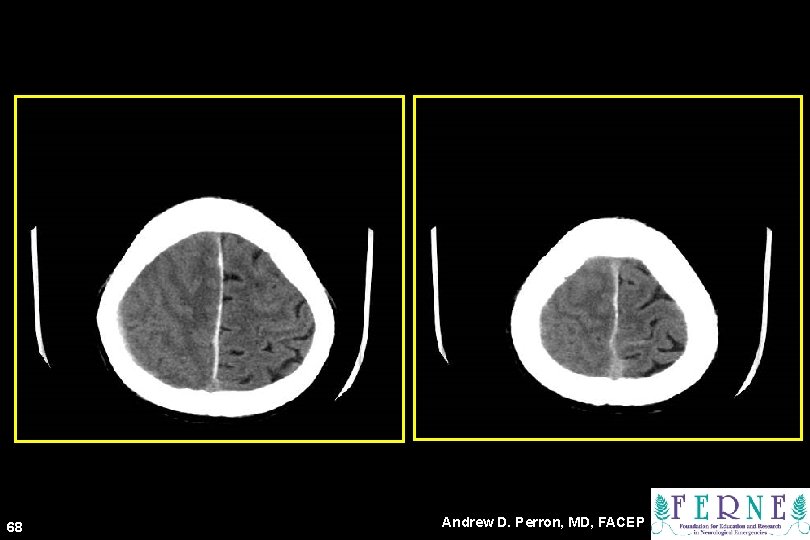

68 Andrew D. Perron, MD, FACEP

Mass Effect 69 Andrew D. Perron, MD, FACEP